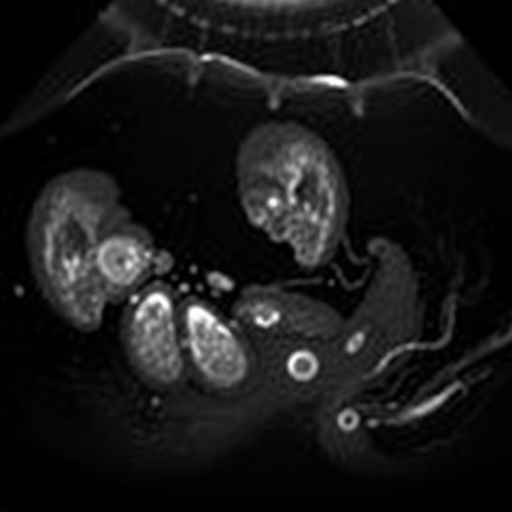

The methodology employed in the study encompassed a robust observational framework involving a substantial cohort of expectant mothers undergoing routine imaging. The researchers meticulously analyzed ultrasound images to measure endometrial thickness accurately. To bolster the reliability of their findings, they adopted advanced imaging techniques that enhance clarity, thereby enabling a more precise assessment of endometrial and ovarian anatomy.

The results of the research were promising. A statistically significant correlation emerged between measured endometrial thickness and the incidence of ovarian cysts during later visits. This connection holds merit, as it suggests that a simple measurement could serve as an early warning signal for potential complications that necessitate closer monitoring. Such findings could prove invaluable in clinical practice, allowing for pre-emptive interventions that could potentially save lives or mitigate complications.